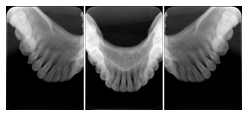

3. A dental provider wishes to capture a series of DICOM IO images for the patient’s dentition. The tooth morphology, teeth are divided into molars, premolars, canines and incisors, and a number of images for each jaw. The anatomic information was captured utilizing the triplet of schema. This standard code sequence is based on ISO 3950-2010, Dentistry - Designation system for teeth and areas of the oral cavity.

Every IO image should have anatomic information either through the primary or modifier sequence.

In most standard cases, images are oriented in structured layouts. These structured displays are useful to be shared between providers for reference purposes.

Table OO.1.1-1 shows structured display standard templates, where Viewset ID is based on the Japanese Society for Oral and Maxillofacial Radiology (JSOMR) classification provided by JIRA (Japan Medical Imaging and Radiological Systems Industries Association, www.jira-net.or.jp). Expected or typical teeth to be imaged location, region and designation codes are based on ISO 3950-2010, Dentistry - Designation system for teeth and areas of the oral cavity. For all the hanging protocols listed in OO.1.1-1, the value to use for Hanging Protocol Creator (0072,0008) is "JSOMR" and the value to use for Hanging Protocol Name (0072,0002) does not include "JSOMR" (e.g., "DL-S001A", not "JSOMR DL-S001A").